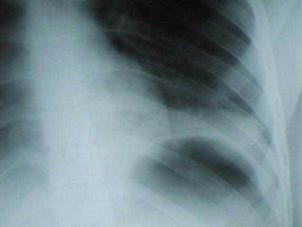

Pneumotorace simplu stang Pneumotorace

simplu stang

Pneumotorace